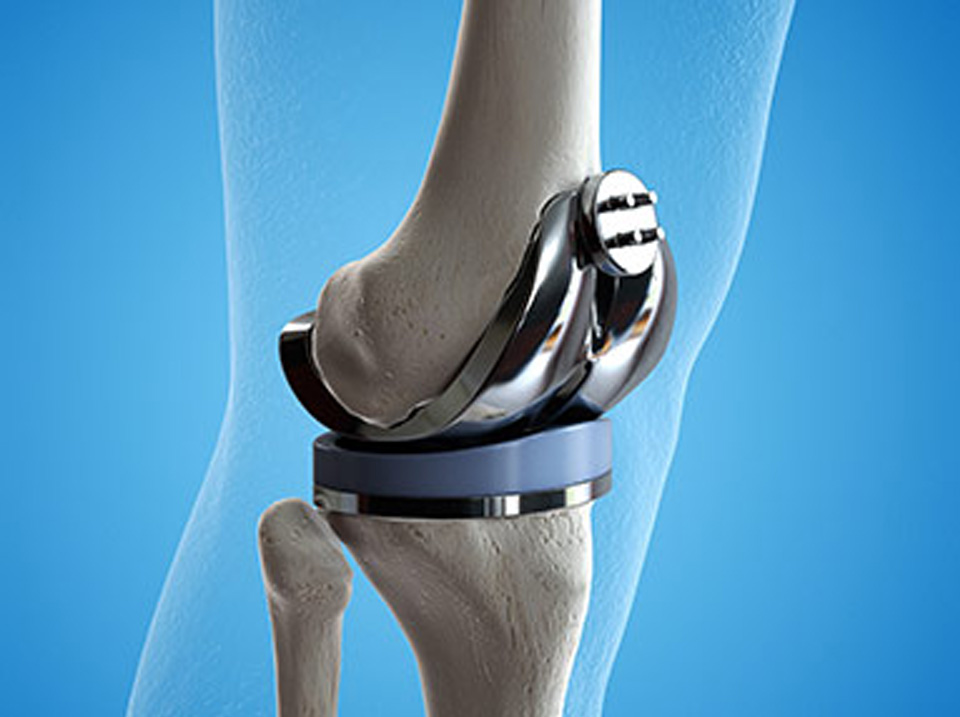

Protez Cerrahisi

Kalça, diz ve diğer eklem protez cerrahisi, eklem replasmanı operasyonları.

2 ay önce

Diz protez cerrahisi sonrası artık rahat yürüyebiliyorum. Dr. Ramin Mirza'nın uzmanlığı ve deneyimi gerçekten etkileyici. Teşekkürler.